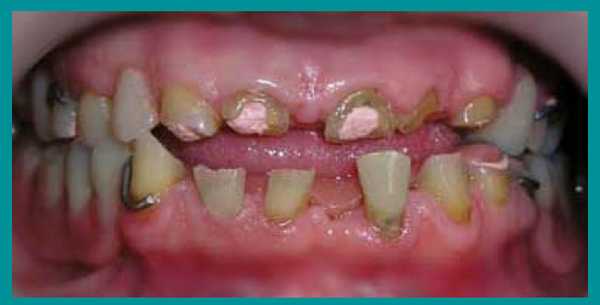

4 этап лечения

После появления необходимой высоты прикуса на передние зубы были изготовлены и установлены пластмассовые корневые вкладки и на них выполнены временные коронки.

Изготовление металлических вкладок пока было преждевременно, так как можно было ошибиться с размером и наклоном в переднезаднем направлении. С появлением временных пластмассовых коронок пациент стал улыбаться, смог не только пережевывать, но и откусывать пищу передними зубами. Так как изменение высоты прикуса происходило постепенно, пациент быстро и благополучно привыкал к создавшемуся положению и явлений дискомфорта не испытывал.